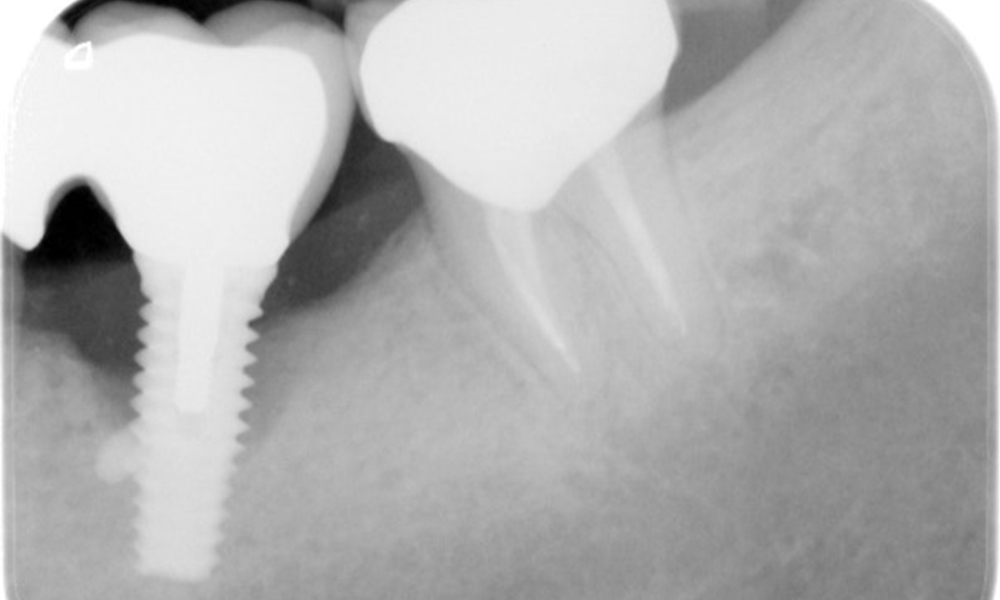

The X-ray images show the progression of bone loss.

The X-ray images show the progression of bone loss in the area of the implant in region 36: dental film from 11.02.2021 (left) and dental film from 18.01.2024 (right).

OPG: 26/02/2024 Dental X-ray: 18/01/2024